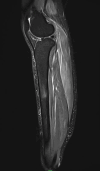

In the era of this pandemic, without any proper and efficacious availability of antiviral agents against the novel coronavirus disease 2019 (COVID-19), vaccines have come as a hope for humankind. Although adverse reactions are common after getting the COVID-19 vaccine, serious or life-threatening side effects are very uncommon in these new emergency-approved vaccines. In this case report, we describe an unusual case of adverse reaction in a patient who received the COVID-19 vaccination. The patient who received the COVID-19 vaccination presented with progressive right lower limb pain and swelling, which further progressed to bilateral shoulder pain and swelling. Ultrasonography, Doppler, and magnetic resonance imaging of right lower limb were done for the patient.